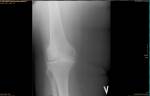

| 06.09.2022 16:30:24 | Евгений Анатольевич Кулинчин Город: Москва (kulinevg@yandex.ru) |

Уважаемый доктор! запишемся на консультацию в 1-ю больницу. есть ли возможность нам помочь при таком снимке(см фото) Прошу Вас оцените возможность . Готовы на все только не эндопротезирование !Помогите. | |

| Ответ: | Добрый день. Решение об объёме операции принимается на основании нескольких критериев. Один из них качественная диагностика. Сделайте пожалуйста ещё МРТ. |